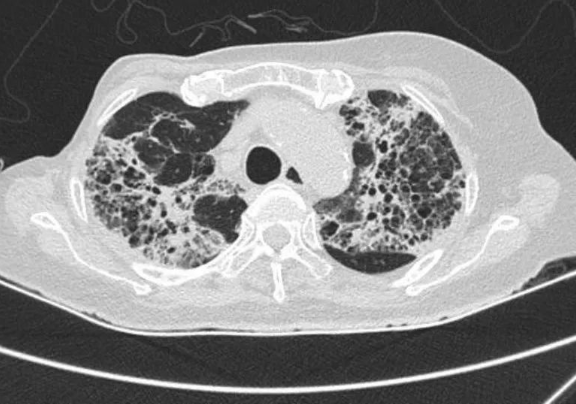

*患者影像檢查

66歲的徐阿姨因"反復(fù)高熱伴呼吸困難"轉(zhuǎn)入我院。該患者既往有乳腺癌手術(shù)史,此次發(fā)病已輾轉(zhuǎn)多家三甲醫(yī)院,診斷為"重癥肺炎、I型呼吸衰竭",曾出現(xiàn)消化道出血等嚴(yán)重并發(fā)癥。轉(zhuǎn)入時持續(xù)呼吸機(jī)輔助通氣,存在嚴(yán)重感染性休克、多器官功能衰竭,病情極其危殆。